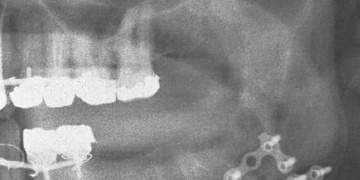

Zlomili mu čelist a v bezvědomí skončil v nemocnici

14. prosince 2018 10:17 , aktualizace 10:20

Další brutální napadení v plzeňských ulicích řeší policisté